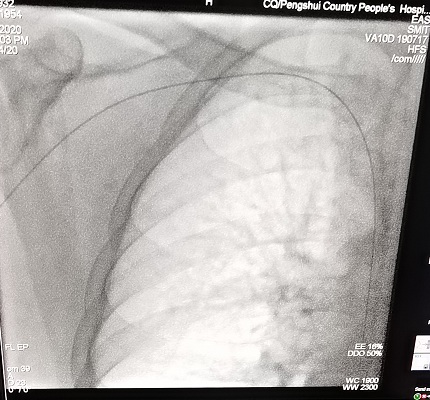

此患者为长期门诊规律透析6年的尿毒症患者,10+天前,患者出现右手肿胀明显,同时有明显的胸壁及右上肢静脉曲张,经我院肾内科主任王业磊的仔细查体并完善相关辅助检查,考虑右锁骨下静脉与头臂干交界处的狭窄。结合958医院对口帮扶专家舒勇主任的会诊意见,经过科室的讨论后决定由舒勇主任和王业磊主任联合为患者行DSA引导下经皮静脉球囊扩张术,2020年5月26日手术顺利完成,患者手部肿胀明显消退,效果十分明显。

手术前 手术后